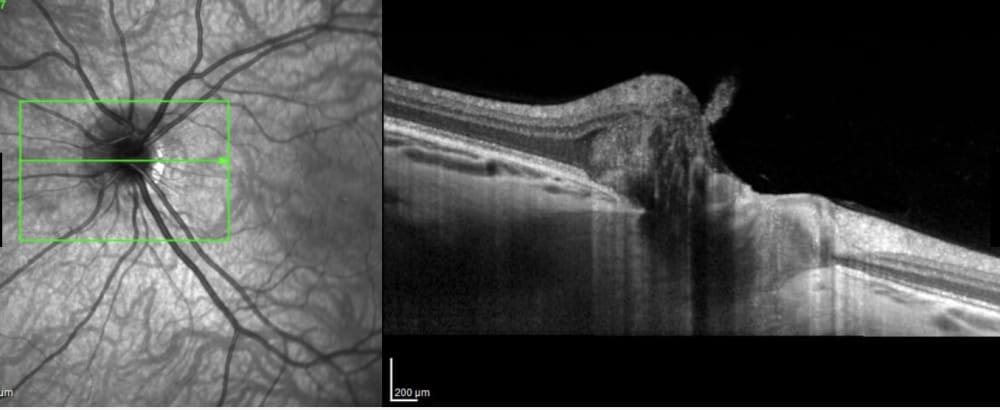

Оптична когерентна томографія (ОКТ) сітківки: сутність методу та його застосування

Оптична когерентна томографія (ОКТ) сітківки - це сучасний неінвазивний оптичний метод візуалізації, що використовується для отримання високороздільних шарових зображень сітківки ока.